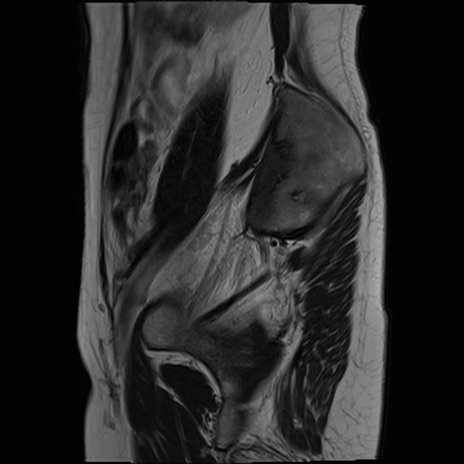

症例39 T2WI(矢状断像)

MRI(4日後)